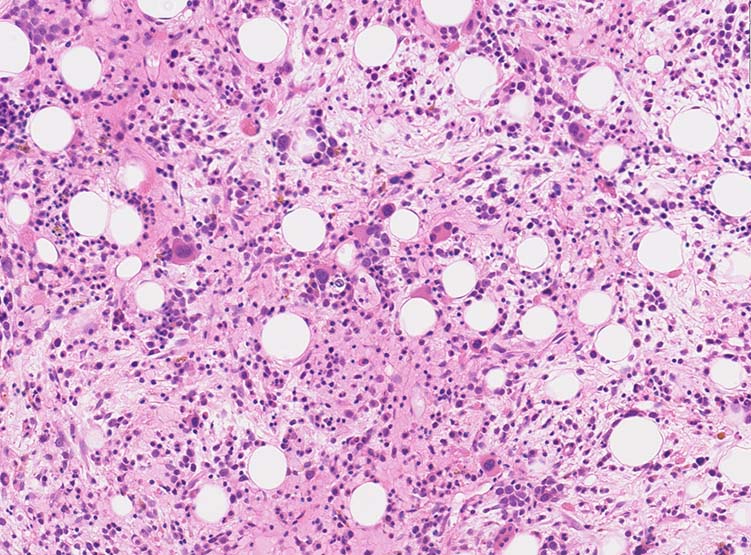

骨髄生検組織

1. 芽球増生の著明な髄様組織をしめすmegakaryoblastic leukaemia

2. 芽球の増殖が乏しく, myelofibrosisのみがめだつ2つのタイプがある。

骨髄生検組織: 骨梁は軽度に肥厚している. 明瞭な硬化像はない. 鍍銀染色でびまん性に線維増生が認められる.

Bone marrow biopsy HE染色: A: 脂肪細胞は減少しているが線維化により造血細胞は疎になっている. B:小型Mgkが散在性に多数認められる.核は類円形, 小型低分葉の細胞が多く, 分離円形核をもつ異形成Mgkが出現している.

C:骨梁に沿って赤芽球が局在している. 通常は顆粒球系細胞が骨梁辺縁に局在する.

骨髄組織所見

正形成髄ないし過形成髄を呈する.

造血巣には, 巨核芽球と種々の成熟段階の異型巨核球が優位に増殖する. 両者の比率は症例によりさまざま.

小型巨核球が一様に増殖する症例では他のAML病型と形態的に区別ができないときがある.

巨核芽球とともに多数の成熟巨核球が増殖する症例もあるが, このときの成熟巨核球は一般に小型で, 低分葉核をもち異形成がめだつ.

微小巨核球が孤在性にあるいは集簇して多数認められる場合もある. クロマチンに濃染する1-2個の成熟核をもち成熟巨核球にみられる淡好酸性細胞質をわずかに有する細胞として見られる. 組織切片で巨核球系と同定するにはCD42b, CD61などの免疫染色が必要になる.

骨髄系, 赤芽球系の幼若細胞や異型細胞が混在することがあるが数はすくない.

骨髄線維症をともなうことがAML-M7の重要な特徴であるが, 必発ではない. 髄様の病変の症例がある.

弾性線維増殖であることが多いが, ところどころに膠原線維の増生を伴うことがある. (鍍銀染色, EVG, Azan染色で評価する)